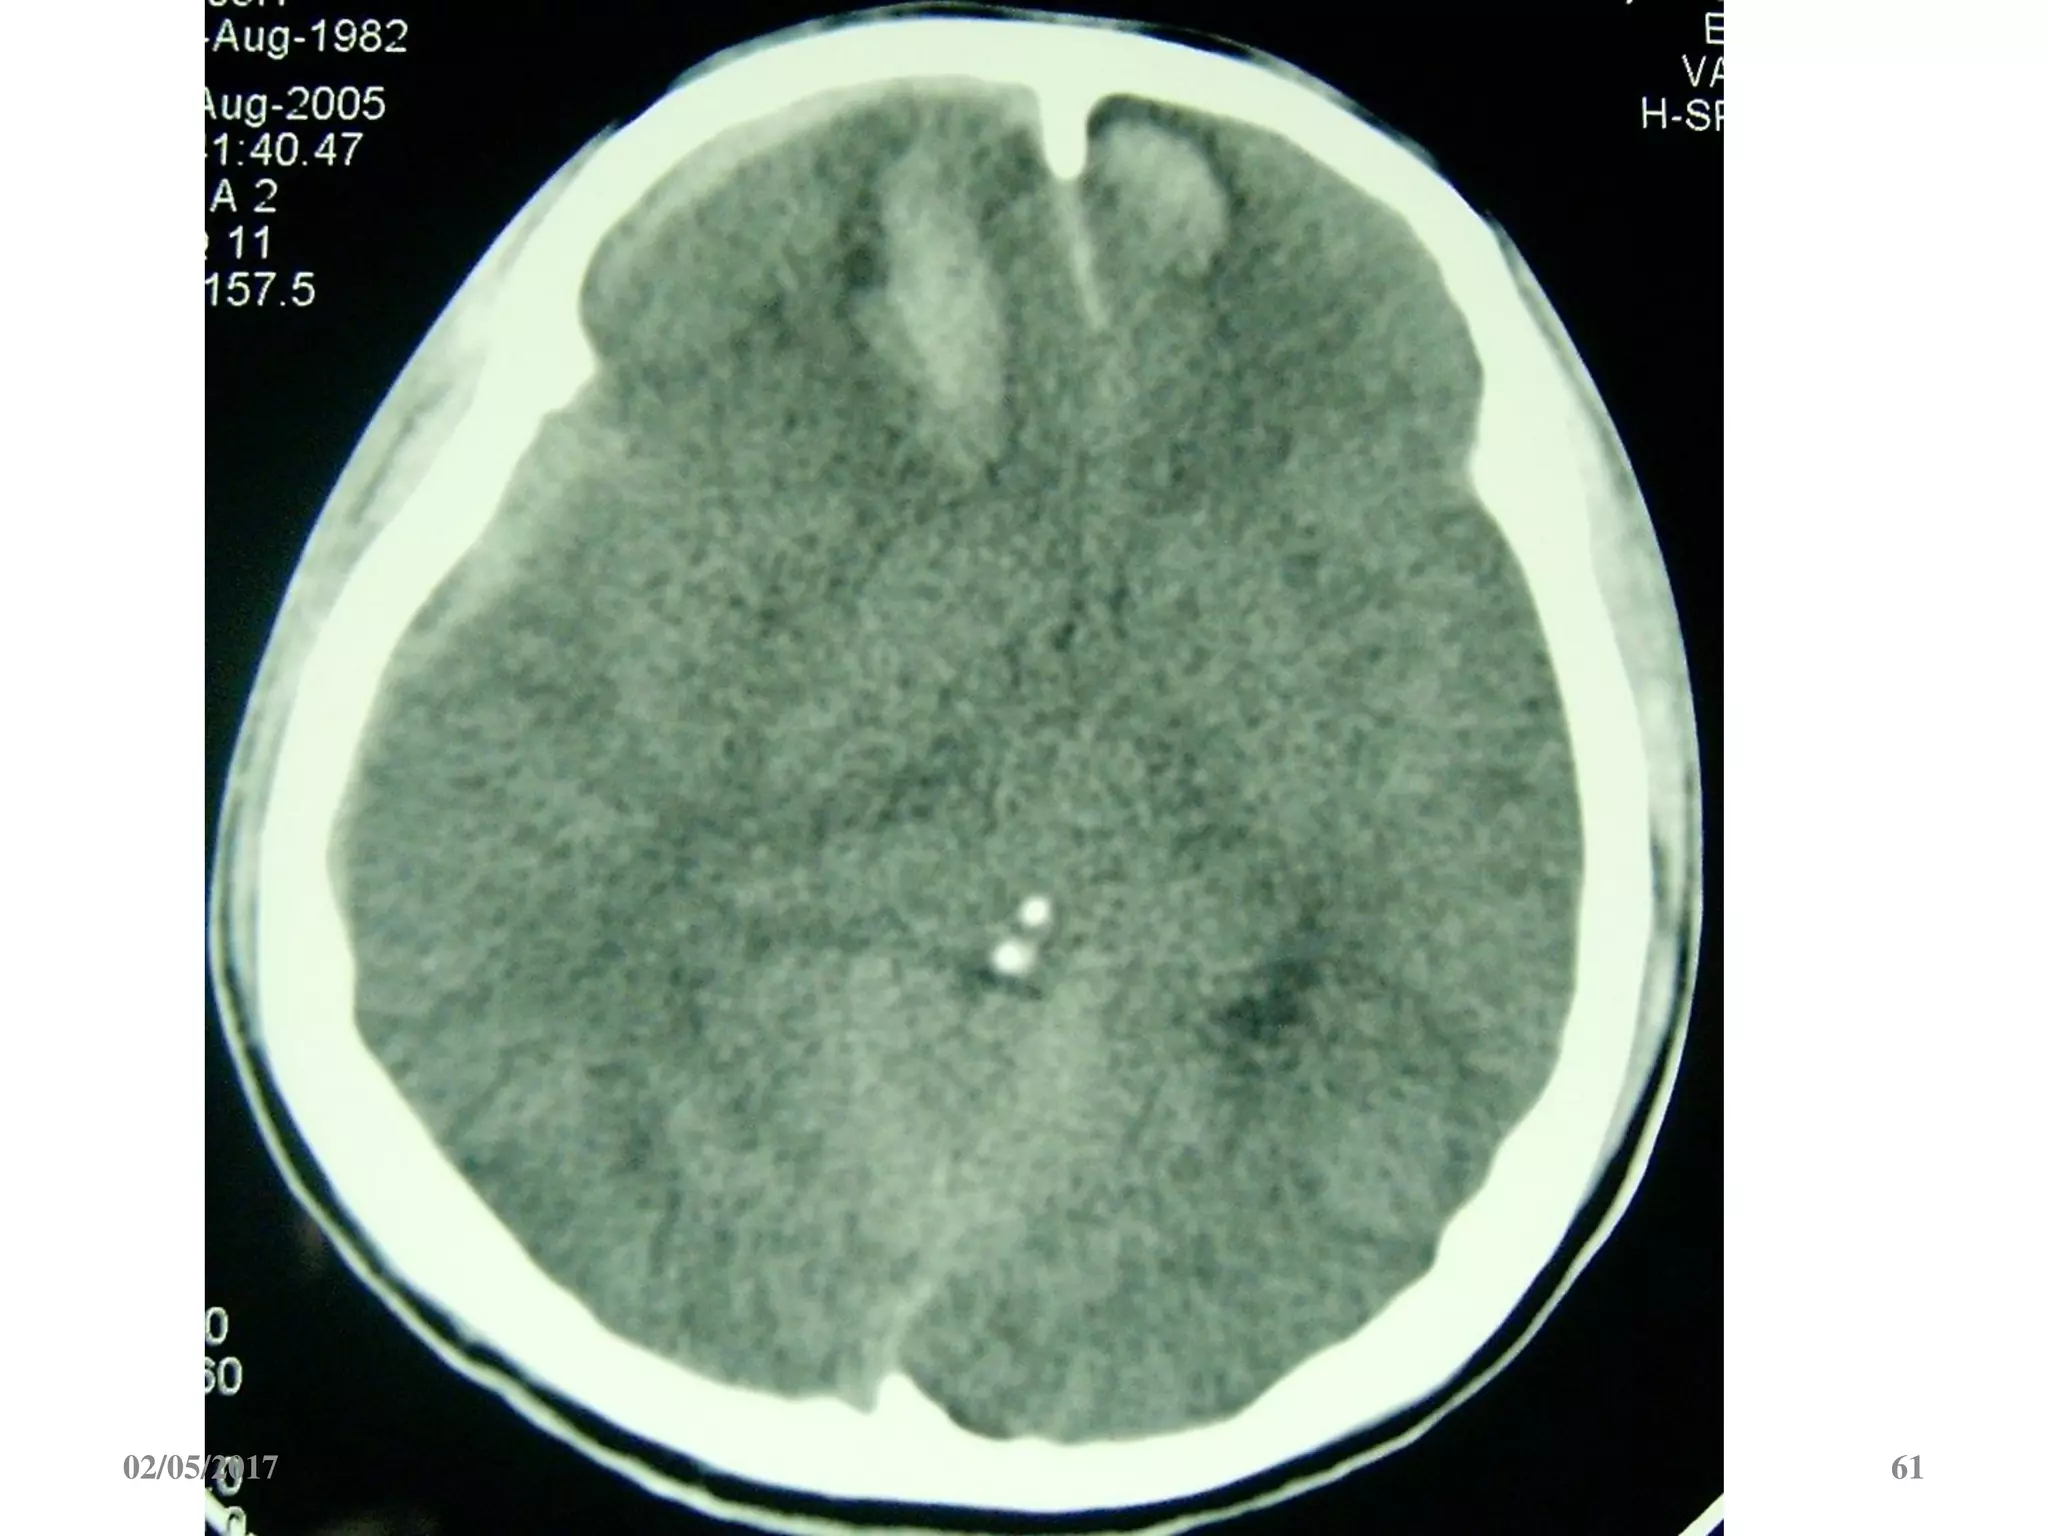

Máu tụ trong não

• Vị trí: trán, thái

dương, đỉnh, chẩm.

• Hình ảnh tăng đậm

độ trong tổ chức não

02/05/2017 60

02/05/2017 61